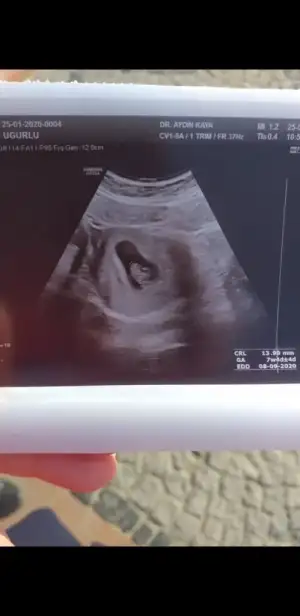

Cok mutlu oldum senin adina canimDoktordan çıktım şimdi ❤Kalbini duyduk çok şükür hiç problem yok çok mutluyum çooooook

Sağol canım benim Normalde 6+2 ama 7+1 dedi doktorum canımCok mutlu oldum senin adina canim

Doktordan çıktım şimdi ❤Kalbini duyduk çok şükür hiç problem yok çok mutluyum çooooook

Merhaba, biz 6+2de kalp atışını gördük ama duymadık, 4 şubatta tekrar gideceğim, zaman geçmiyor bir türlüSelam kızlar rabbim kısmet ederse bende eylül annesi olacağım inşallah bebislerinizin kalp atışını duydunuzmu acaba

Merhaba bizde 7+2 de gördük ama duymadık 10 şubatta tekrar gidicem inşAllahSelam kızlar rabbim kısmet ederse bende eylül annesi olacağım inşallah bebislerinizin kalp atışını duydunuzmu acaba